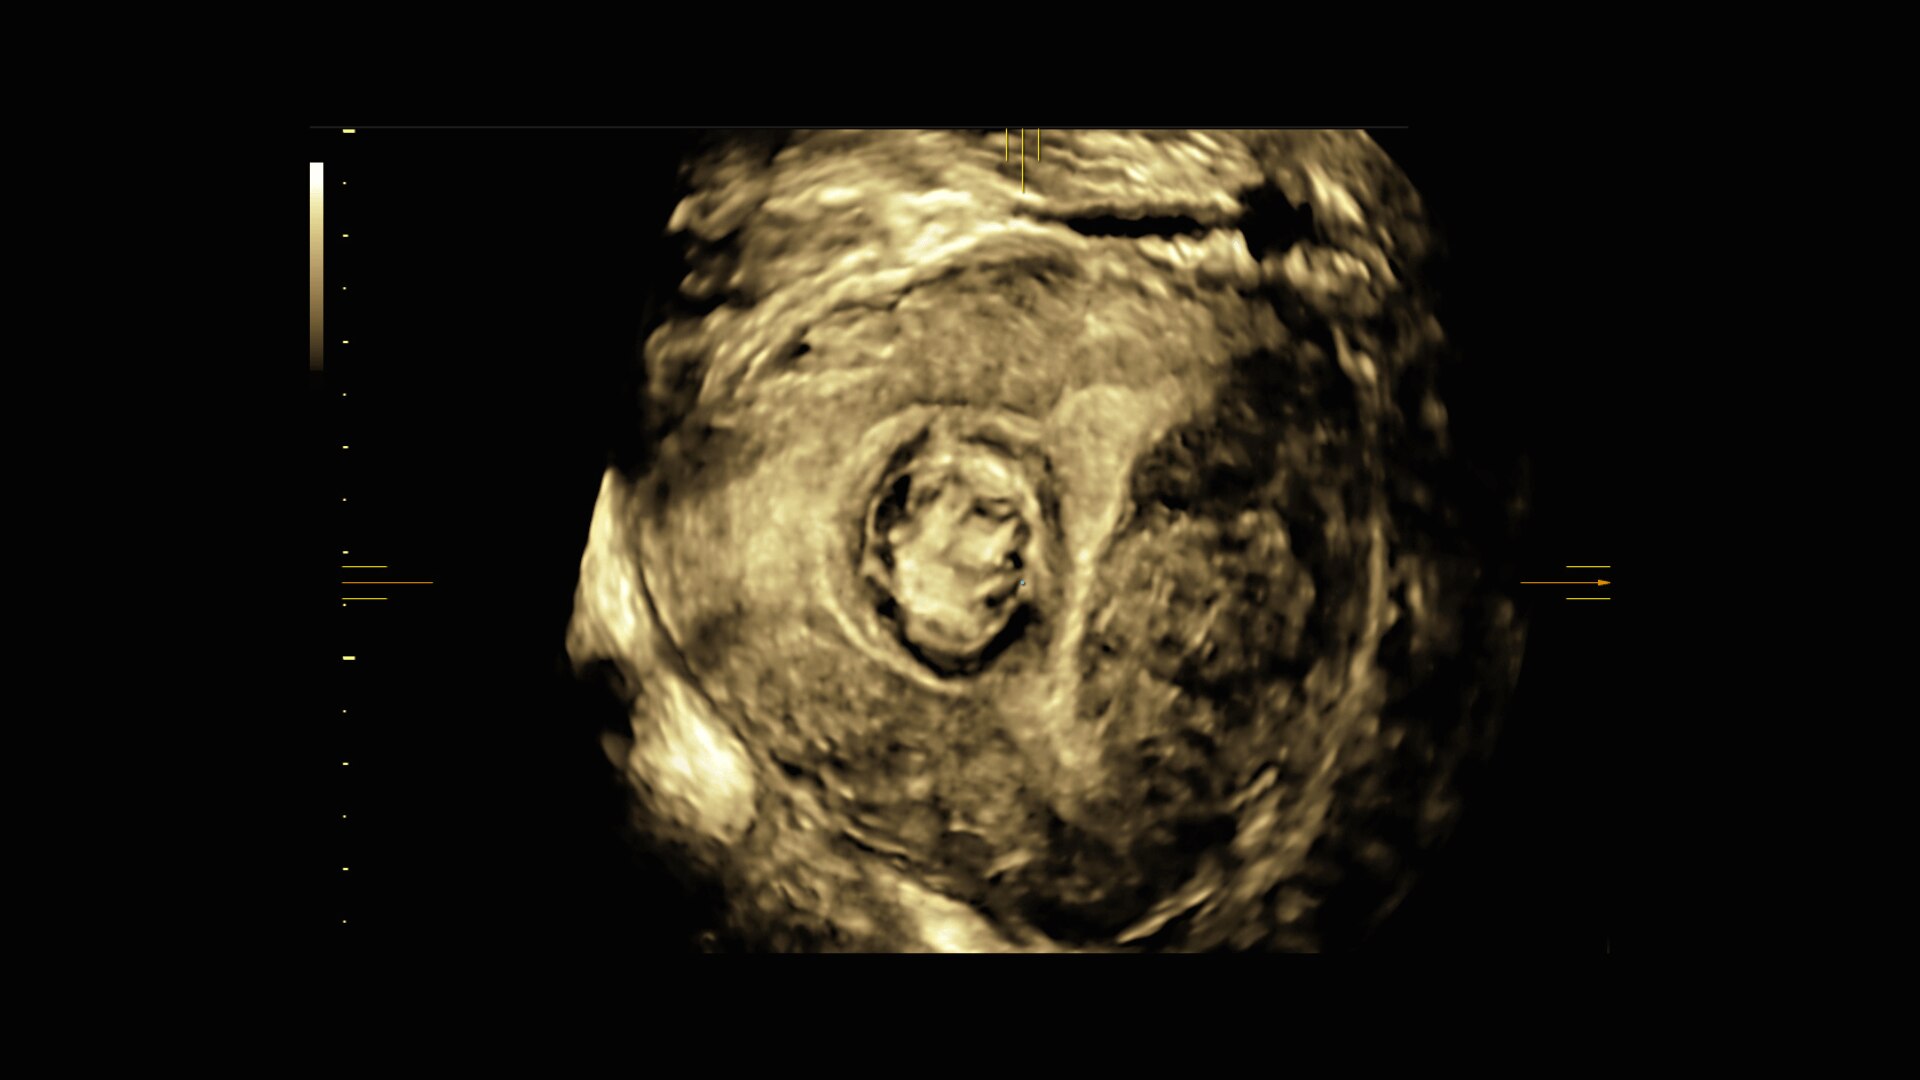

Image quality

Excellent images that are easy to acquire

Image quality is everything in ultrasound

The Voluson Performance 18 delivers high-resolution, detailed imaging with one-touch optimization for effortless scanning—helping you deliver quick, confident answers across a wide range of patient.